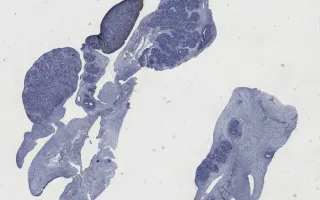

This fetus also had gonads with an indeterminate appearance on gross examination, corresponding histologically to gonads with both ovarian and testicular differentiation (“ovotestes”).

The overall findings in this fetus included increased growth parameters, congenital diaphragmatic hernia, nephroblastomatosis, and ovotestes.

This slide shows PLAP stain, highlighting germ cell components. See Related Content section for other stains, specimen photograph and kidney slides: